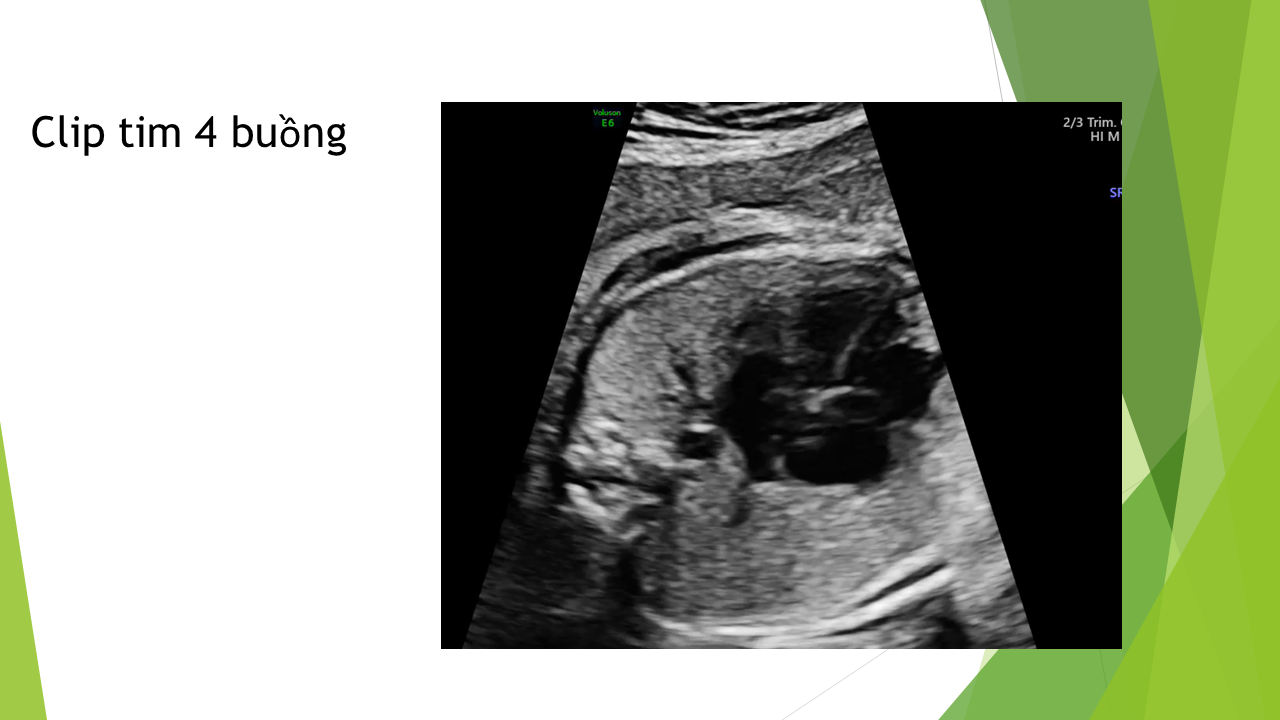

Siêu âm tim thai bằng phương pháp LEVY và STOS. 5-4-3-2-1